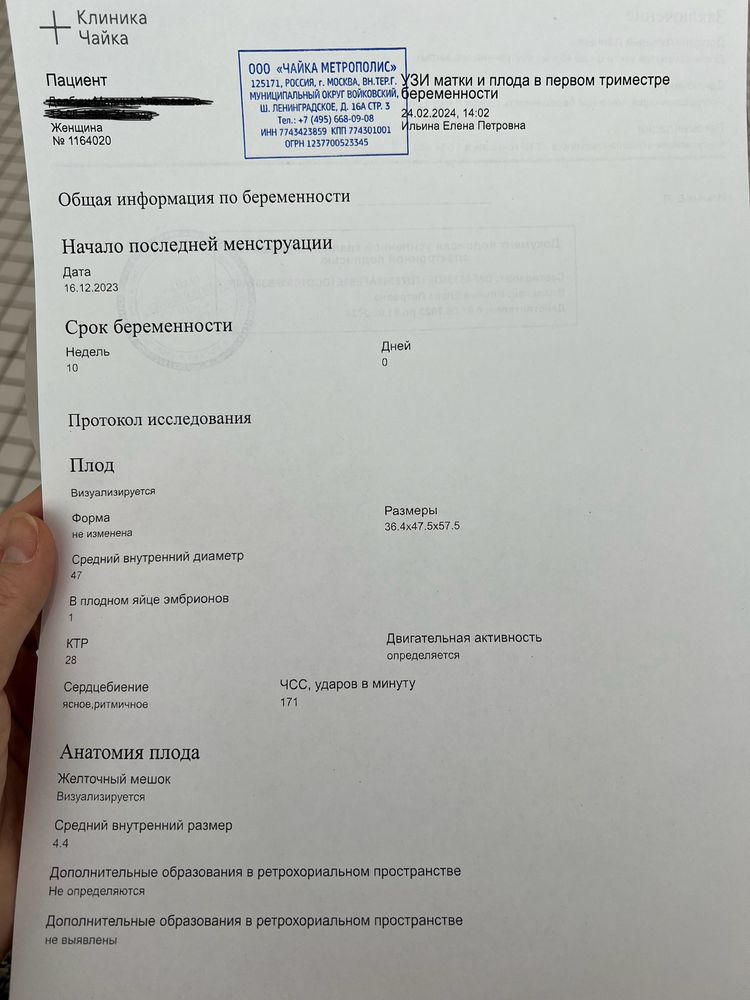

Здравствуйте! Дорогие дамы, прикрепляю 2 узи от 13.02.2024 и от 24.02.2024. Нормально малыш вырос? Узистка странно написала на первом узи, что малыш по ктр на 8 недель и 3 дня, хотя аппарат показывал 8 недель ровно. Сегодня у меня (24.02.2024) 10 недель ровно, а аппарат показал 9 недель и 4 дня. На самом первом узи в 6 недель и 3 дня мне аппарат показывал, что малыш по размерам на 6 недель ровно. То есть, везде стабильно 3 дня разница с акушерским сроком. Сегодня аппарат показал ЧСС 177, но узистка написала в протоколе 171, почему-то.